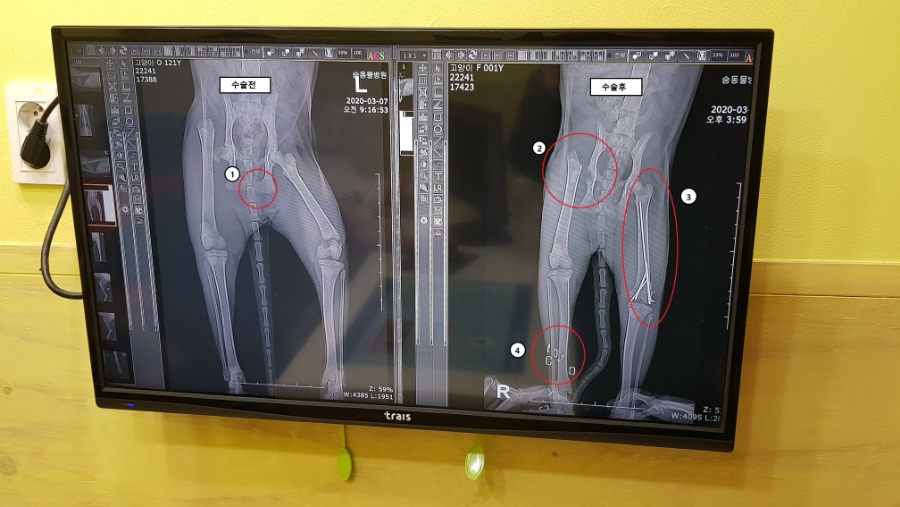

3¿ù6ÀÏÀÌ¿´´ø°Í °°Àºµ¥ »õº®¿¡ ¾ß½Ä¸Ô°í ¿À´Â ±æ¿¡ Åͳο¡ »õ³¢°í¾çÀ̰¡ È¥ÀÚ °É¾î°¡´õ¶ó°í.. ¸¾ÀÌ ³Ê¹« ¾ÈÁÁ¾Æ¼ µ¹¾Æ°¬´Âµ¥ ¾Ö°¡ µÞ´Ù¸® ÀüºÎ¸¦ ¸ø½á¼ 24½Ã°£ µ¿¹°º´¿ø °¡·Á°í µ¥¸®°íÀÖ´Â ¿ÍÁß¿¡ ¿ìÃøº¸Á¶¼®¹Ø¿¡ µé¾î°£°Ü ¿¡¾îÄÁÇÊÅ͹ØÀ¸·Î,´Ù½Ã¹æµÚ·Î ±×·¡¼ ÀÌ·¸°Ô±îÁö ¶â¾ú´Ù ¾îÂî¾îÂî 24½Ã°£µ¿¹°º´¿ø¿¡ µ¥¸®°í°¡¼ Áø·á¸¦ ¹Þ¾Ò´Âµ¥ ÀÌÁ¤µµ¿´°í ƯÈ÷ ¿ìÃø ¹«¸°ñÀýÀÌ »ó´çÈ÷ ½É°¢ÇÑ»óÅ¿´À½ ³»°¡º¸±â¿£ ¿ÞÂÊ °í°üÀý °ñ¹ÝÀÌ ´õ ¹®Á¦ÀΰͰ°Àºµ¥ Àú°Ç ±×³É ±×·¯·Á´Ï º¸½Ã´õ¶ó ±×·¡¼ ¼ö¼úÇØ¾ßÇϴµ¥ 300°¡±îÀÌ µç´Ù°í ÇÏ´õ¶ó ±æ°í¾çÀ̰í 300Àº ³Ê¹« Å«µ·À̶ó.. ±×·¡¼ »ý°¢ÇÒ ½Ã°£À» °¡Áø µÚ¿¡ ´Ù½Ã ¿Â´ÙÇϰí,±×³¯Àº º´¿ø¿¡¼ ´Ù¸®¿¡ »ó󳪼 ±«»ç·ÎÁøÇàµÇ°íÀÖ´Â °÷À» µå·¹½ÌÈÄ ºØ´ë·Î°¨°í ÀÔ¿ø½ÃŰ°í µ¹¾Æ¿Ô´Ù ±×¸®°í ´ã³¯ °á±¹¿£ ¼ö¼ú½Ã۱â·ÎÇÏ°í ¿øÀå½ÜÀ̶û ´Ù½ÃÇѹø »óÀÇÇߴµ¥ ±æ³ÉÀ̰í,³»°¡ Ű¿ì´Â´ë½Å¿¡ ÇÒÀοÀÁö°ÔÇØÁÖ½Å´Ù°í ±×·¡¼ ³ª¿Â °¡°ÝÀÌ ¤¾ ¤¾.. ¼ö¼úÈÄ Àß µÆ´Ù°í ÇÏ´õ¶ó..¤¾¤¾µ·ÀÌ¿ÀÁö°Ô³ª°¬³× ±Ùµ¥ ¾ÆÆÄ¼ µß±¼°íÀÖÀ½¤»¤»¤» »ç¶÷µµ »À°Çµé¸é ¾ÆÇµ¥ Àú°í¾çÀÌ´Â ÇÏüÀüºÎ¸¦ °¥°¥Çߴµ¥ ¾È¾ÆÇø®°¡.. ±×¸®°í ÀÌ°Ç ÃÖ±Ù©ÀÌ´Ù Áý¿¡ °¾ÆÁö¹Û¿¡¾ÈŰ¿öºÁ¼ °í¾çÀÌ´Â Àß ¸ð¸£Áö¸¸ ±×·¡µµ °¡Á·À̵ɰŴϱî Àß Å°¿öº¸±äÇØ¾ßÁö ±Ùµ¥ ³Ñ¸ðºñ½Î´Ù ¤Ð¤Ðµ·À̾ø¾ß.. ¾Æ¹«Æ° °³ºØÀ̵鵵 ÁÁÀºÇÏ·çµÇ°í ±Â¹ãÇØ ¾Æ ÀÌ°Ç ¿ì¸® °¾ÆÁö© ps£©³ª ±æ³ÉÀÌÇÑÅ× ¹äÁִ»ç¶÷ ¾Æ´Ô 3ÁÙ¿ä¾à 1.±æ³ÉÀÌÁÖ¿ò 2.¼ö¼úÇϴµ¥300µç´ÙÇØ¼°í¹ÎÇÔ 3.°Á ¼ö¼ú ¤¡ ÂøÇÏÀÚ³Ê.. ¤Ð¤Ð